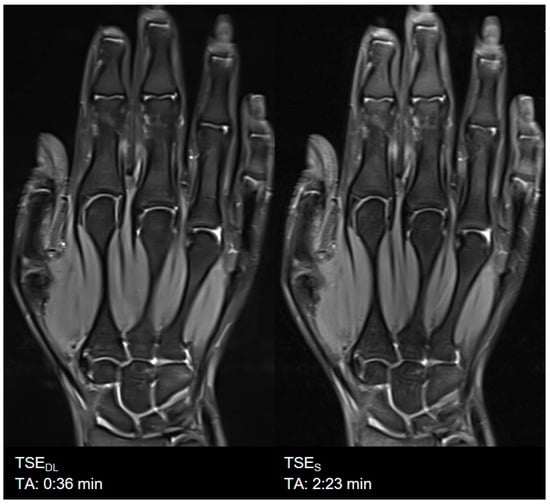

| Hand | TSES | TSE PD FS | coronal | 2:23 | 200 | 0.5 × 0.5 × 2.0 | 2 | 1 | 0 | 3000 | 41 | 150 | 121 | 13.6 |

| axial | 4:40 | 180 | 0.5 × 0.5 × 2.0 | 2 | 2 | 0 | 3310 | 42 | 150 | 121 | 13.9 | |||

| TSEDL | TSE PD FS | coronal | 0:36 | 200 | 0.5 × 0.5 × 2.0 | 1 | 1 | 3 | 3000 | 44 | 150 | 119 | 14.7 | |

| axial | 1:23 | 180 | 0.5 × 0.5 × 2.0 | 1 | 2 | 2 | 3190 | 42 | 150 | 119 | 14.1 |